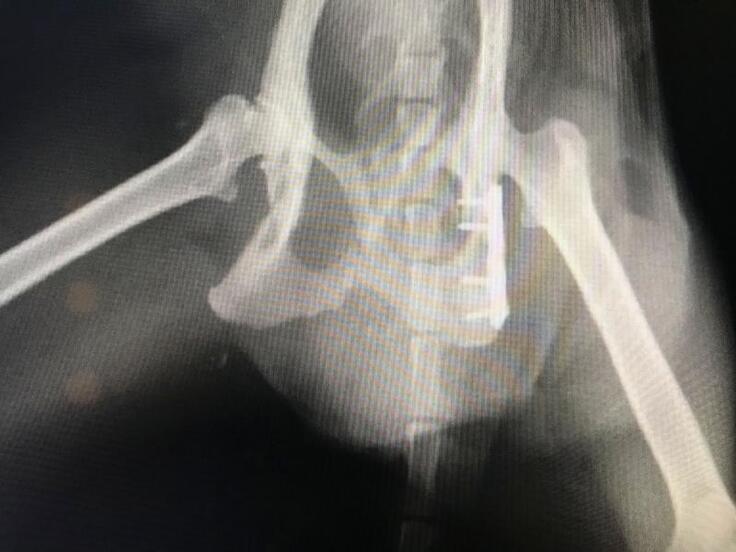

脚が立たないようなので仔猫2匹とクロちゃんを一緒に保護して動物病院で診察してもらうと、骨盤骨折していました。

初診のレントゲンでは骨盤の左側が骨折という診断で手術を受けましたが、手術後のレントゲンで右側も骨折していて、粉砕骨折しているという結果でした。

交通事故に遭ったのだと思いますが、骨盤骨折して立てない動かない脚を前脚だけで引き摺って仔猫の元に帰ろうともがいて頑張って家の前まで帰って来ていたクロちゃん、なんとかうまく骨がつながって普通に歩いて走ってジャンプできるようになって欲しいと思います。

骨盤骨折しても必死で仔猫の元に帰えろうとしていたクロちゃんの骨盤骨折(粉砕骨折)を手術して元のように歩いて走ってできるようにしてやりたい。